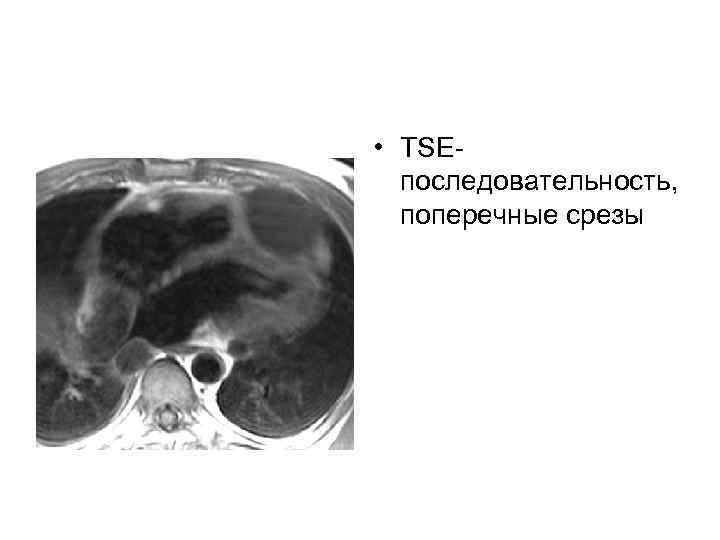

• TSEпоследовательность, поперечные срезы